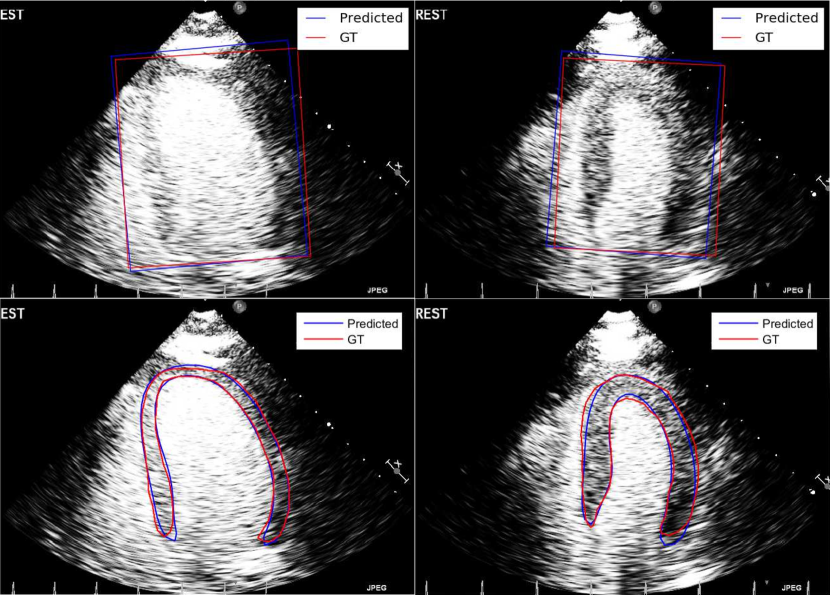

Refer to caption

(a)

(b)

Figure 6: Segmentation accuracy results of the various approaches for (a) Dataset1𝐷𝑎𝑡𝑎𝑠𝑒𝑡1Dataset1 and (b) Dataset2𝐷𝑎𝑡𝑎𝑠𝑒𝑡2Dataset2. The ends of the whiskers represent the lowest and highest data point within 1.5 times the interquartile range. Top black brackets indicate the difference between the two approaches is significant using the paired t-test.

Figure 7: Top: Visual comparison of the bounding boxes estimated by CNN (blue) and the ground truth (red). Bottom: Visual comparison of the final contours estimated by our fully automatic approach M2 (blue) and the ground truth (red).

In this experiment, we evaluate the accuracy of the CNN bounding box detection algorithm against the manual ground truth. We measure the detection error as 𝑩detected𝑩groundtruth=δ𝑩=(δBx,δBy,δBw,δBh,δBθ)subscript𝑩𝑑𝑒𝑡𝑒𝑐𝑡𝑒𝑑subscript𝑩𝑔𝑟𝑜𝑢𝑛𝑑𝑡𝑟𝑢𝑡𝛿𝑩𝛿subscript𝐵𝑥𝛿subscript𝐵𝑦𝛿subscript𝐵𝑤𝛿subscript𝐵𝛿subscript𝐵𝜃{{\boldsymbol{B}}_{detected}-{\boldsymbol{B}}_{groundtruth}=\delta{\boldsymbol{B}}=}(\delta{B}_{x},\delta{B}_{y},\delta{B}_{w},\delta{B}_{h},\delta{B}_{\theta}). Table II shows the bias and standard deviation of the error for each bounding box parameter. All parameters show mean values close to zero, indicating small systematic bias. Localization uncertainty of (Bw,Bh)subscript𝐵𝑤subscript𝐵({B}_{w},{B}_{h}) is higher than that of (Bx,By)subscript𝐵𝑥subscript𝐵𝑦({B}_{x},{B}_{y}). This indicates the CNN is less accurate in determining the scale of the bounding box compared to its position. CNN also has high localization precision for predicting the bounding box orientation (Bθ)subscript𝐵𝜃({B}_{\theta}). Qualitatively, the top row of Fig. 7 shows the manual and CNN-detected bounding boxes on some example MCE images.

Fig. 6(a) presents the segmentation accuracy results (Jaccard, MAD and HD) and Table III reports the evaluation on clinical indices such as endocardial area and myocardial area. ASM does not perform well because it uses a simple intensity profile model to search for the best landmark position. This model is not adequate for noisy MCE images. RF can provide a much stronger and discriminative intensity model. In M1, we apply our segmentation method using the CNN bounding box detection algorithm (BBCNN) and the RF with SM features. However, we replace the last shape model fitting step with a Canny edge detector to obtain a binary edge map as the final segmentation. This gives better results than the ASM but the final segmentation is not regularized by global shape constraint. To improve the results further, shape model fitting is added in M2 to give our fully automatic segmentation approach. It combines the local discriminative power of RF with the global shape constraint imposed by the shape model. The fitting guides the segmentation in regions where the RF probability map has low confidence predictions. It also ensures the final segmentation is a smooth and coherent contour that represents plausible myocardial shape. The bottom row of Fig. 7 shows the final myocardial contour predicted by M2. The method is able to segment the myocardium accurately even in the presence of shadowing and attenuation artifacts which result in unclear epicardial border. In M3, we trained three separate RF models and shape models for the three different apical chamber views. There is a small improvement in results since each model learns more specifically the different anatomy of each view although a general model that includes all views (M2) is also quite robust. Since there are less training data for each view model in M3, we expect the results to improve with more data. In M4, we replace the CNN bounding box in M2 with manual bounding box (BBManual). This results in a semi-automatic approach which accurately removes any myocardial pose variations and achieves the best results in the final segmentation.